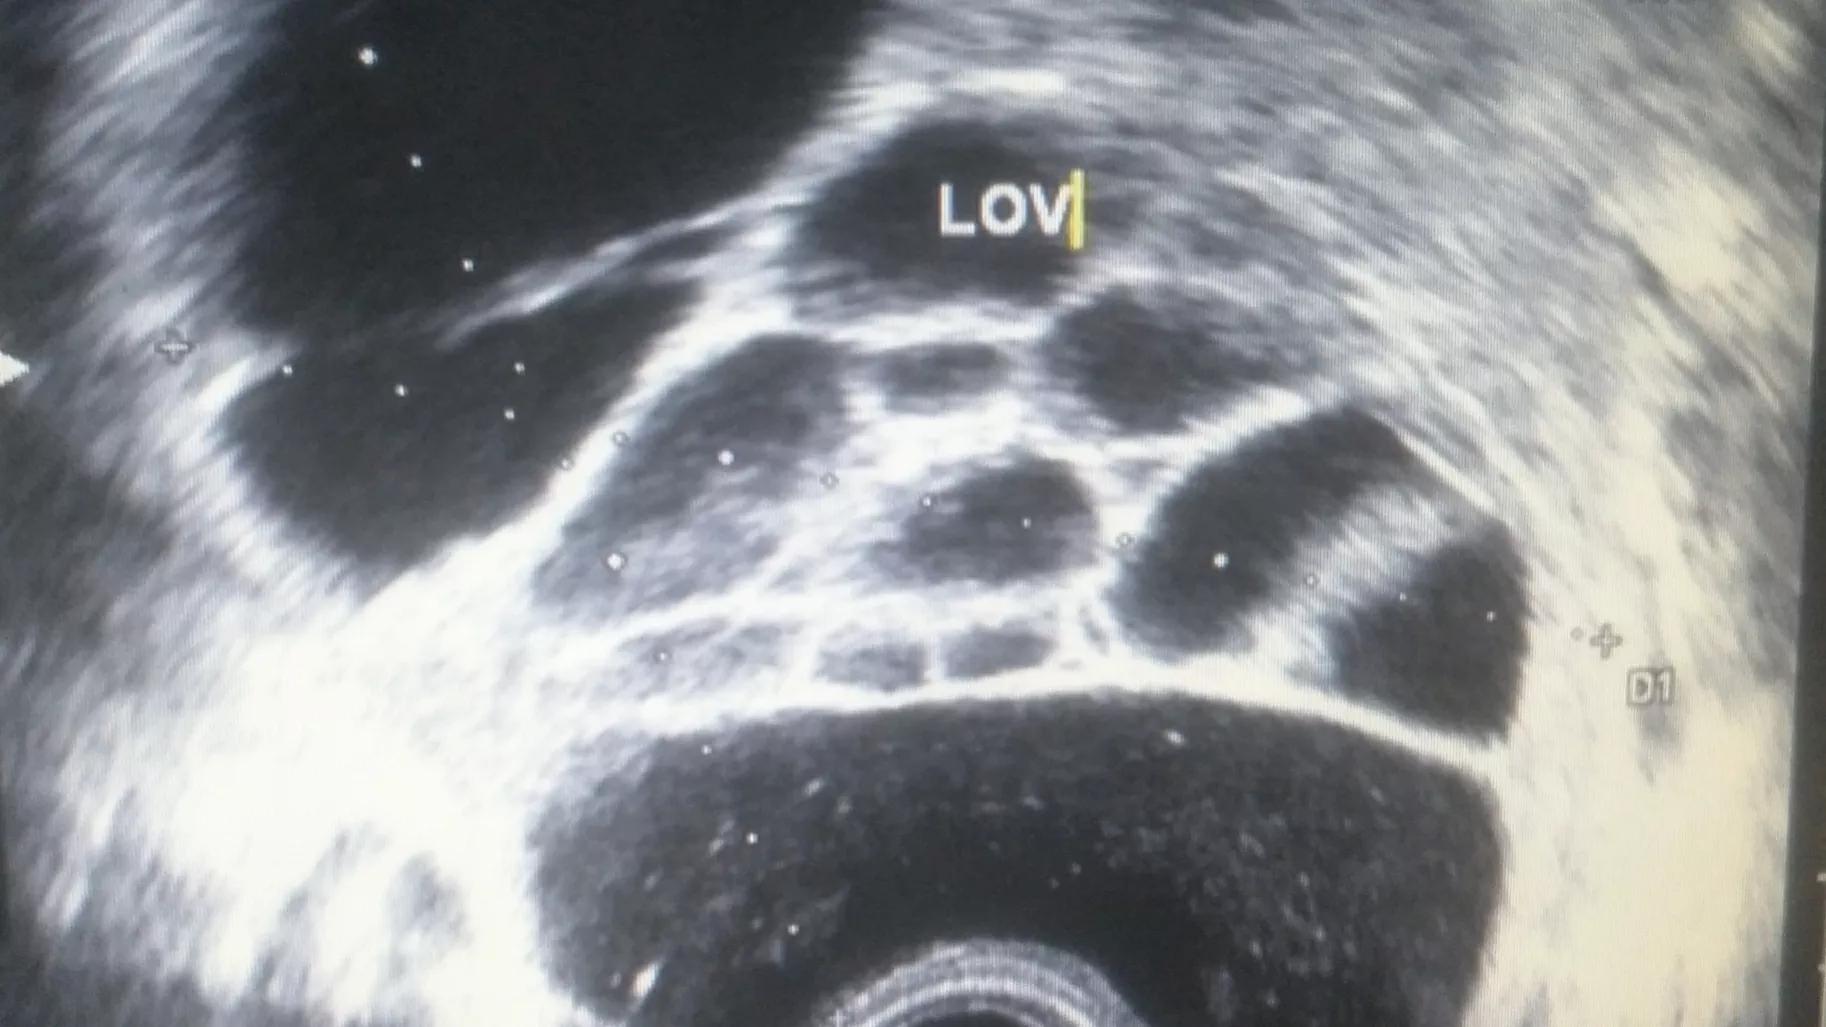

核磁检查示胃区周围发现多个肿大的淋巴结,这就意味着癌细胞己向周围器官转移一一中晚期胃癌了。

肿大淋巴结的MRI图像